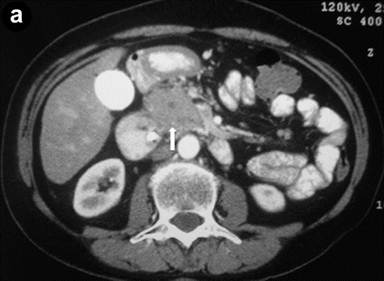

A 64-year-old woman presented with painless jaundice, itching and a recent diagnosis of diabetes mellitus. Serum IgG4 levels were elevated (310 mg/dL). Contrast-enhanced axial CT (portal phase) revealed that the pancreatic head was substantially enlarged, with an ill-defined hypodense area (arrow) (Image 5a). Linear EUS (Image 5b) showed a focal roundish echopoor lesion of 23 mm (arrows) in the pancreatic head (ph), and the common bile duct (arrowheads) had a diffusely thickened wall, with a "sandwich-pattern" (Image 5c). The EUS-FNB (arrow points to the needle) of the echo-poor lesion is shown in Image 5d.

|

Image 5 |